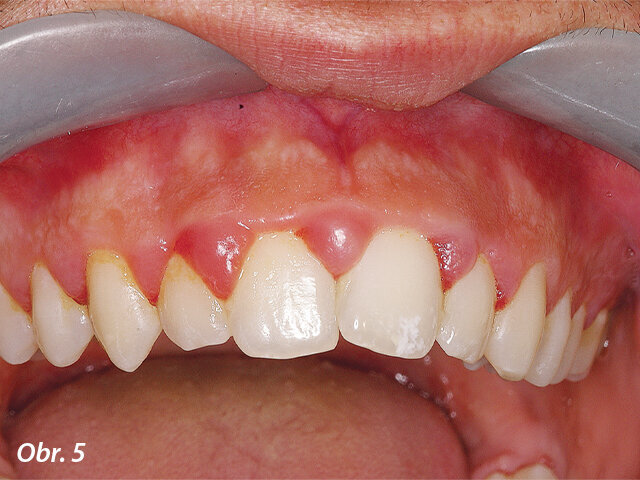

Jak je patrno z obrázku 1, pacientka se dostavila do mé ordinace s lokalizovanou hutnou hyperplastickou oblastí dásně, která byla potvrzena klinickým vyšetřením. 31letá pacientka měla elegantní oblečení a čisté, dobře udržované ruce a nehty. Stěžovala si, jak je těžké danou lokalizovanou oblast čistit a popisovala, že snaha o vyčištění bolí a způsobuje krvácení, především při použití dentální nitě. Došlo k narušení kontinuity hladkého vzhledu gingivy, díky čemuž vypadal její povrch nerovně a esteticky rušivě.

Hutná hyperplastická tkáň interproximálně mezi zuby 23 a 24. Hyperplasticky změněná tkáň omezovala přístup do interdentálního prostoru, v důsledku čehož nebyla pacientka schopna provádět v inkriminované oblasti řádnou ústní hygienu.